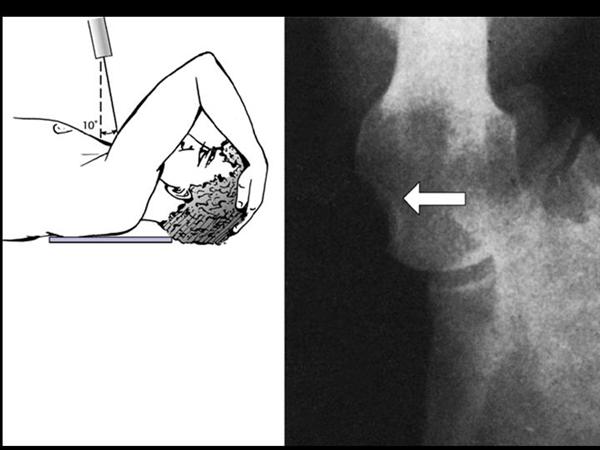

7. Stryker notch view : Hill-Sachs lesion

8. West point axillary view : anterior inferior glenoid, Bankart lesion